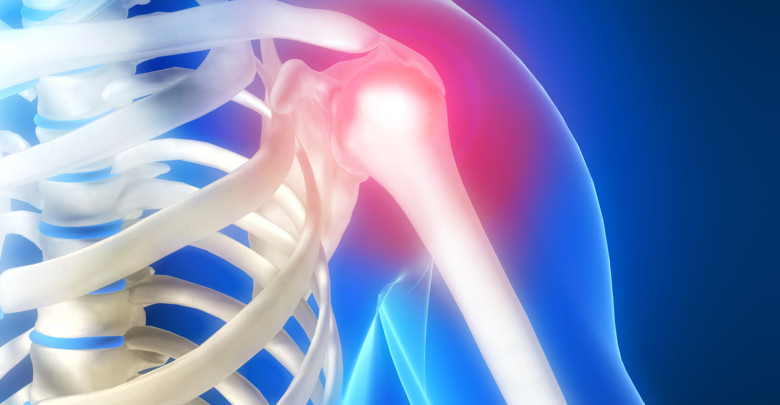

Μία σύντομη περιγραφή της φύσης της άρθρωσης:

Η άρθρωση αποτελείται από την σύνδεση τριών οστών, της κλείδας της ωμοπλάτης και του βραχιονίου. Κάθε οστό έχει ειδική κατασκευή ώστε να προσδίδει σταθερότητα και μεγάλο εύρος κίνησης. Στην ωμοπλάτη προσφύονται 17 μυς παρέχοντας κινητικότητα και σταθερότητα στην κατά τα άλλα ασταθή άρθρωση του ώμου. Έχει τα χαρακτηριστικά μιας άρθρωσης τύπου σφαίρας – πλάκας, καθώς η επιφάνεια της ωμογλήνης (τμήμα της ωμοπλάτης), είναι ρηχή και μικρή σε σχέση με την κεφαλή του βραχιονίου. Ο γληνοβραχιόνιος σύνδεσμος παίζει τον πιο σπουδαίο ρόλο στην άρθρωση του ώμου διότι εμποδίζει την πάνω από το φυσιολογικό κίνηση του ώμου. Οι πρωτεύοντες μύες του ώμου είναι ο δελτοειδής, ο υποπλάτιος, ο υπερακάνθιος, ο υπακάνθιος, ο ελλάσον στρογγυλός και ο μείζον στρογγυλό.